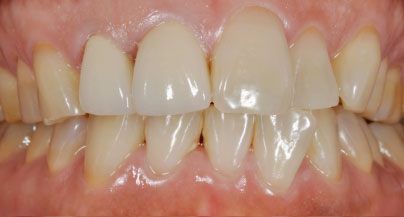

画像の患者様は歯の色と矢印で示された差し歯の色と適合の改善を希望されていました。

最初に約10日間のホワイトニングをして歯の色を改善しました。

次に差し歯の交換を変化した綺麗な歯の色に合わせて交換しました。

全体として約3週間くらいで治療が完了致しました。

とても自然な仕上がりになりました。